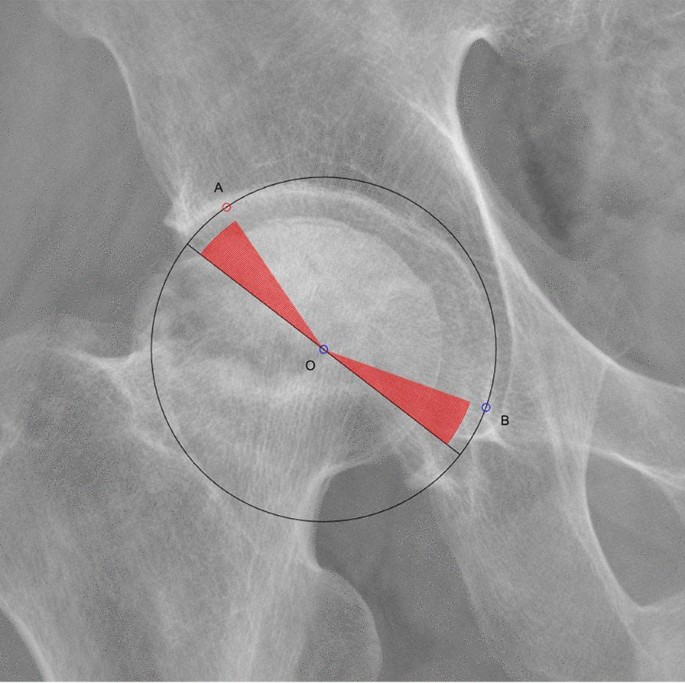

(4) In the dots_LU, a point closest to the d_LU from the boneedge_LU was found, named A;

(5) In the dots_MD, a point closest to the d_MD from the teardrop_BT was found, named B;

(6) The acetabular cup circle passed through A and B, so the acetabular cup center O was located on the mid-perpendicular line of AB; for the hemispherical acetabular cup, the ∠AOB was 180 − (18 + median_th_MD), for the sub-hemisphere/super hemisphere acetabular cup, if the center angle of the acetabular cup was angle_cup, then ∠AOB was angle_cup − (18 + median_th_MD); the diameter of the acetabular cup was calculated as d_cup_templating = L/sin(∠AOB/2), where L was the distance between AB. In addition, the coordinates of the center O of the acetabular cup was calculated and named as center_cup_templating; (Fig. 8).

Determining the center and radius of the cup

To help understanding our templating method, we first simplify the templating conditions: all cups are hemispherical (the center angle of the cup is 180°), and the size of all the cups is about the same (close to the median 52 mm).

If it is known that a circle passes through two points A and B, it can be known that the center O of this circle is located on the perpendicular line of the line segment AB. If we also know ∠AOB, we can determine the position of the center O and the radius of this circle. In fact, there are two solutions for the circle center, which are located on both sides of the line segment, but considering the application scenario of the pelvic X-ray, the circle center O must be positioned below the line segment AB, so there is only one reasonable solution. To calculate the radius of the cup circle, we need to first determine A, B, and ∠AOB, and then determine O, and then the length of the AO is the radius of the cup.

On the AP X-ray of the pelvis, A is the lateral superior intersection of the cup and the inner wall of the acetabulum. The distance between it and the lateral edge of the acetabulum is d_LU. By measuring the d_LU on postsurgery X-ray of all 406 cases, the median of d_LU is obtained. When templating a new preoperative AP X-ray of the pelvis, as long as we know the coordinates of the lateral edge of the acetabulum and the contour of the nearby acetabular edge, combining with the value of median_d_LU, the ideal position of A can be estimated (A is located on this contour and its distance from the lateral edge of the acetabulum is median_d_LU). In a similar way, the ideal position of B, the medial inferior intersection of the cup and the inner wall of the acetabulum, can also be obtained.

By measuring the th_MD on postsurgery X-ray of all 406 cases, the median of this angle can be obtained (median_d_MD); the lateral uncoverage should not exceed 20%. It can be known that the average coverage ratio is 10%, then the ideal angle on the lateral side should be 180° × 10% = 18°, so the ideal ∠AOB should be equal to 180° − (18 + median_d_MD).

In this way, A, B and ∠AOB are obtained, and then the position and radius of the cup can be calculated.

The above is a simplified templating process. In clinical application, some cups are sub-hemisphere or super-hemisphere, we need to adjust the center angle of the cup, which will affect the value of ∠AOB (See templating step 6 in "Appendix"). In addition, median_d_LU and median_d_MD is suitable in the cases when the cup size is equal to median_cupsize. If the measured cup size is not equal to median_cupsize, we need to scale median_d_LU and median_d_MD (See templating step 3). Because we do not know the templating results in advance, the ideal value of cup_size/median_cupsize is also unknown, therefore, we let the computer try different cup_sizes repeatedly until the templating result becomes satisfactory (see templating step 7).